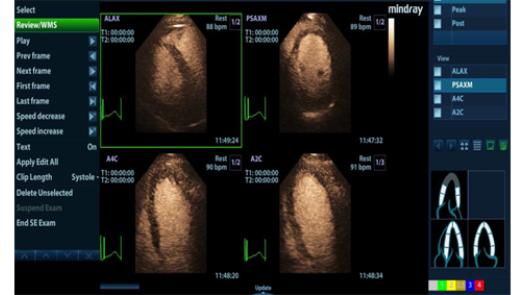

Dedicated and professional solutions